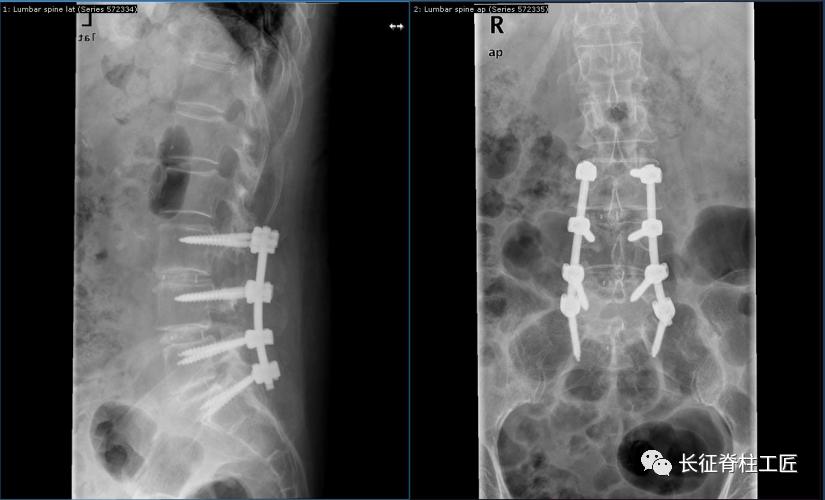

脊柱外科史国栋主任带领团队详细讨论,决定行椎管减压植骨融合内固定术。秉持微创的理念,术中通过精确的切口设计、肌肉组织的保护、手术时间的控制、后侧韧带复合体的保留等措施,在开放的手术中微创的完成了手术。

腰椎管狭窄手术核心是椎管及神经根的减压,减压术后要进行脊柱稳定性重建,以防止术后脊柱失稳的发生,椎管减压植骨融合内固定术应用于复杂型的腰椎管狭窄患者。微创的理念下开放手术具有以下优势:

术前严格查体和影像学检查,特别是MRI检查,确定责任节段,再根据腰椎退变情况,确定要手术的节段范围。